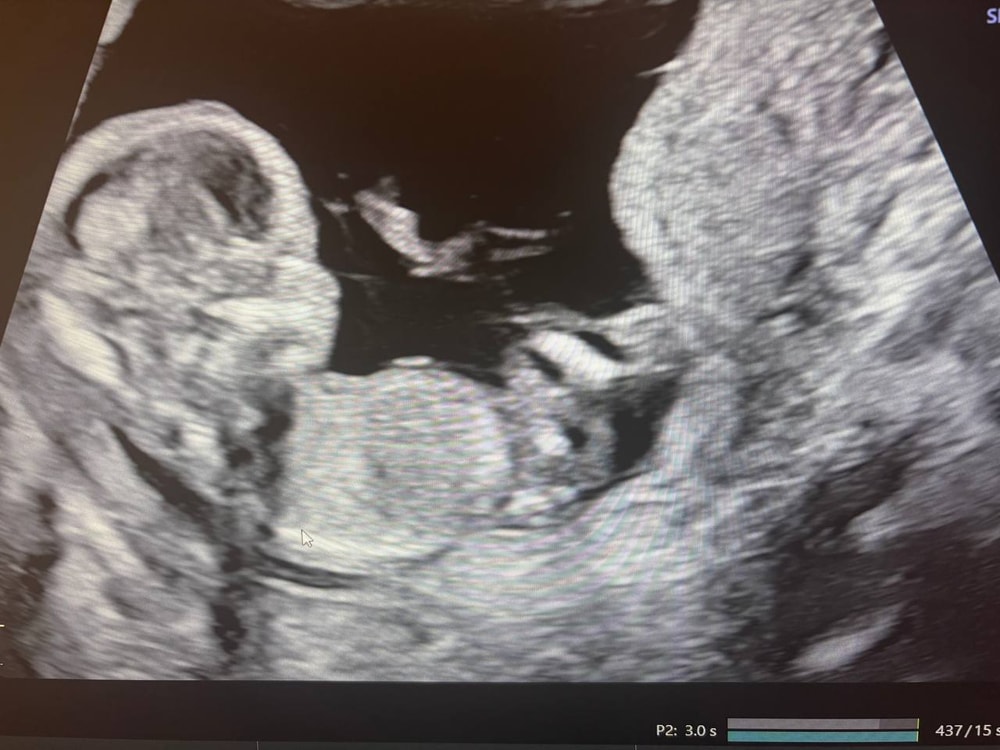

Девушки в регистратуре оказались очень милыми, все рассказали, да и в целом персонал мне понравился. Нам сказали, что от врача зависит разрешит ли мужу зайти тоже посмотреть и только в конце пускают. Немного расстроились изначально, но в итоге оказалось зря. Мне померили давление и потом отправили на УЗИ. Делали его мне около получаса, малыш показался во всей красе изначально. И так повернется, и сяк, и ручкой помашет и пальчики в рот положит (см. фото 1,2). Врач сказала, что малыш отлично развит для срока, все у него в норме, послушали сердечко, посчитали пальчики, похвалили наш профиль, сказали, что красивый))))) Зовут нашего папу тоже посмотреть и тут начинается самое интересное. Как только муж садится и начинаем смотреть, булочка, устав от внимания, демонстративно отворачивается и мы во всей красе лицезреем попку и спинку))) ну вот спасибо))) Врач уже и так, и так пыталась растормошить его, но максимум на что удалось его подбить, это посмотреть на нас через плечо, видимо с мысль "да отстаньте вы уже от меня" (см. фото 3). Но было прям очень забавно это, особенно учитывая тот факт, что это уже не первые его(ее) прятки с папой. То допплером при нем сердечко не могу найти, то сейчас вот спрятался.